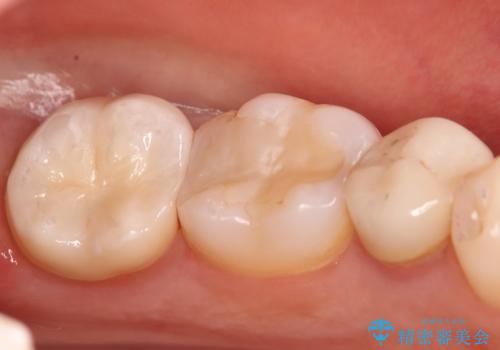

奥歯に虫歯があると言われた セラミッククラウンでキレイで長持ちする歯へ

担当医 榊原康平